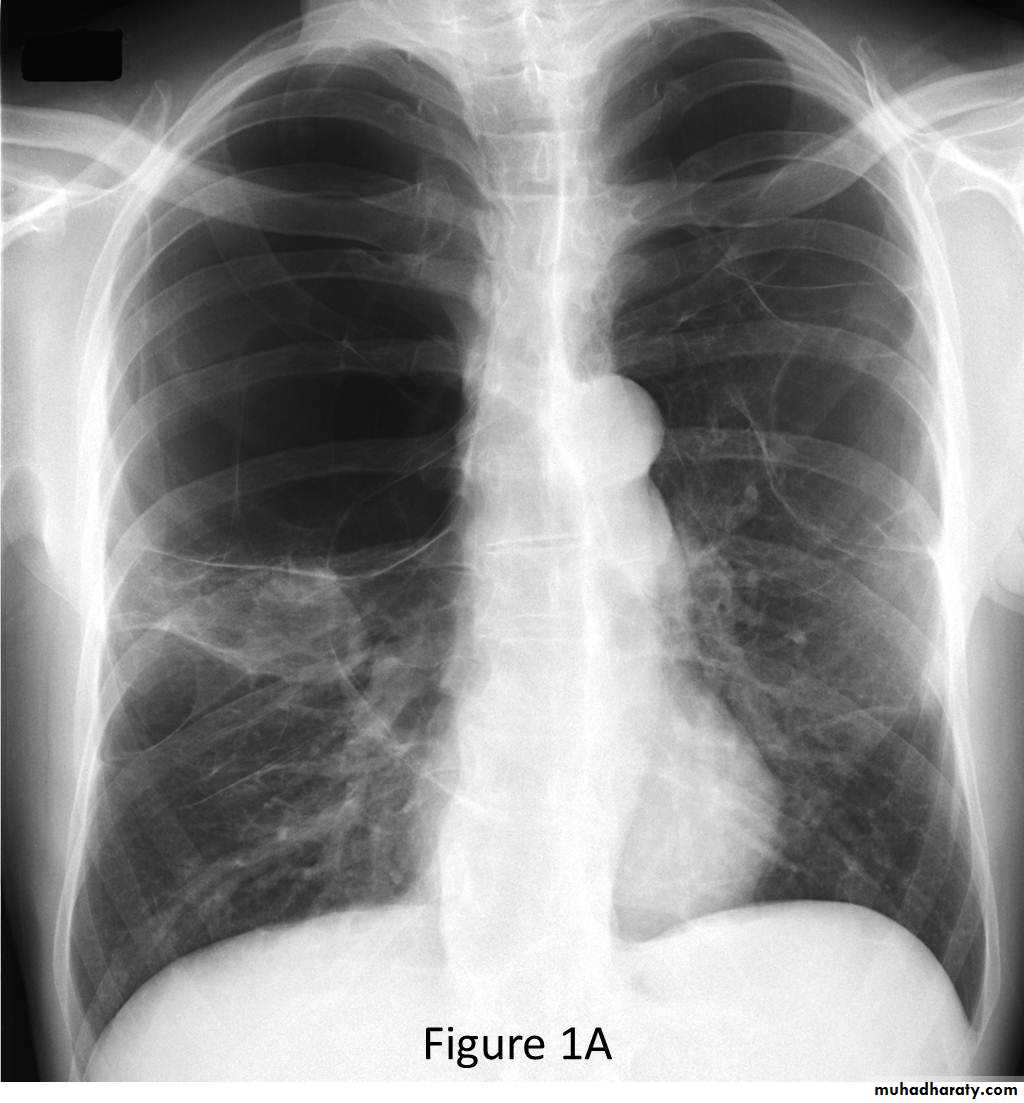

• CXR: lung surrounded by thick irregular pleura with multiple nodules with extension to nearby structures.